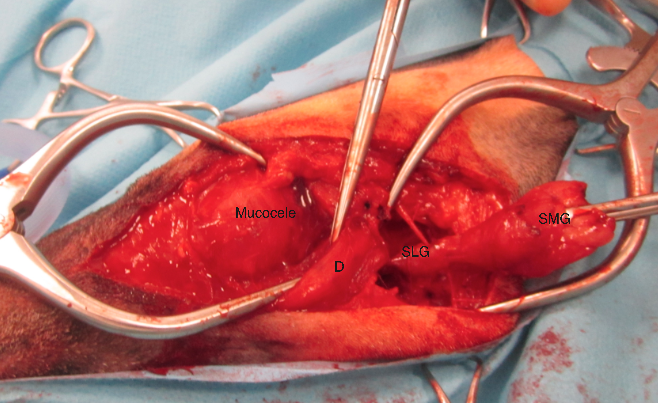

- Although these swellings can be temporarily alleviated with either simple drainage or marsupialization of the ranula, the only definitive treatment is excision of the offending salivary gland tissue usually through either a ventral or ventrolateral approach. A ventral approach gives best exposure (fig 3). The submandibular (SMG) and sublingual (SLG) glands are intimately associated with each other and are usually removed together. Their combined ducts course dorsal to Digastricus (D) and it is important to continue dissection beyond this point, usually to the level of the lingual nerve rostrally. The affected duct can usually be seen entering the sialocele cavity and this confirms that the correct glands have been removed. The sialocele itself does not have to be dissected out but can be simply drained at the time of surgery back to questions >>